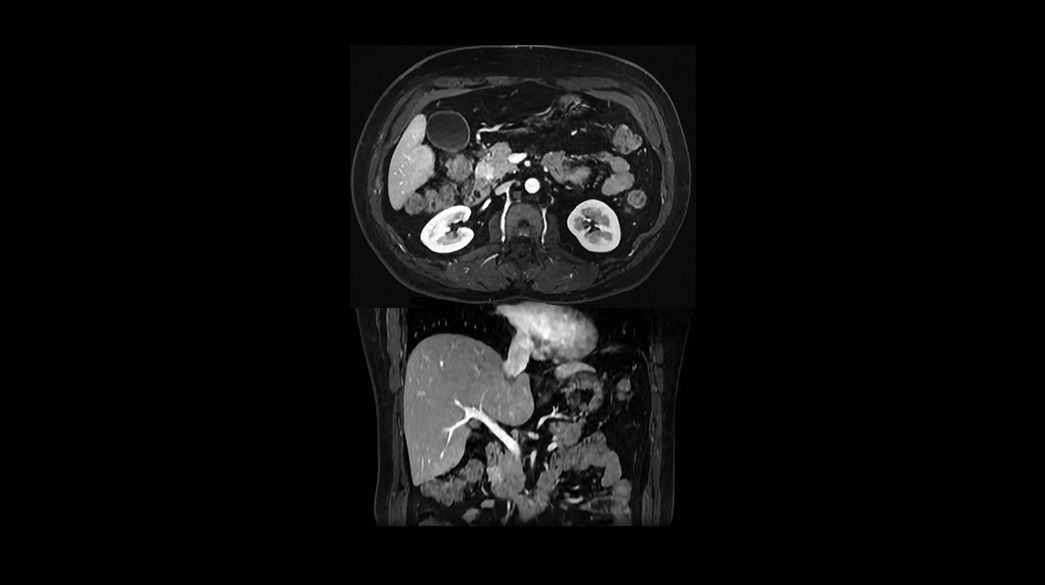

Oncology MRI for SIGNA™

Oncology MR imaging techniques to capture anatomical and morphological data with robust tissue contrast, motion-insensitive and high temporal and spatial resolution for oncological assessment.

Clinical Oncology

Oncological MRI imaging applications

Diagnostic confidence and consistency